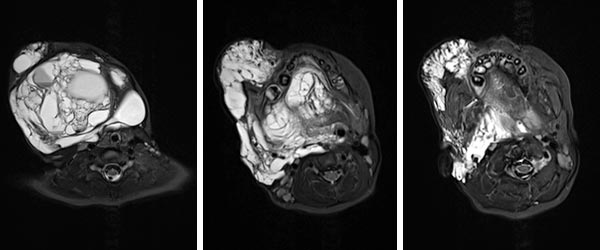

MRI (axial; T2-weighted; fat-suppressed) at 2 years of age shows the lymphatic malformation as a severely hyperintense (white) mass. The extension reaches into the deep soft tissues of the neck. Oropharynx and hypopharynx are clearly constricted. In this situation, there is a threat of upper airway obstruction if the swelling increases. This can be fatal.